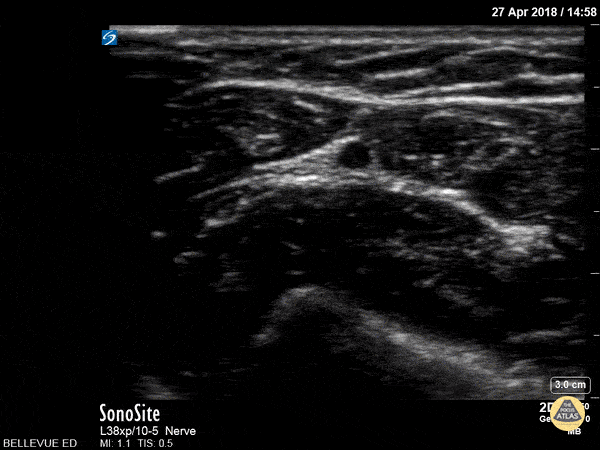

The ulnar nerve is located medial (ulnar) to the ulnar artery. It is best seen by following the ulnar artery in transverse proximally up the arm; eventually a bright hyperechoic triangle will be visible traveling away from the artery. (left arm seen here) Hannah Kopinksi and Dr. Lindsay Davis - NYU Emergency Medicine